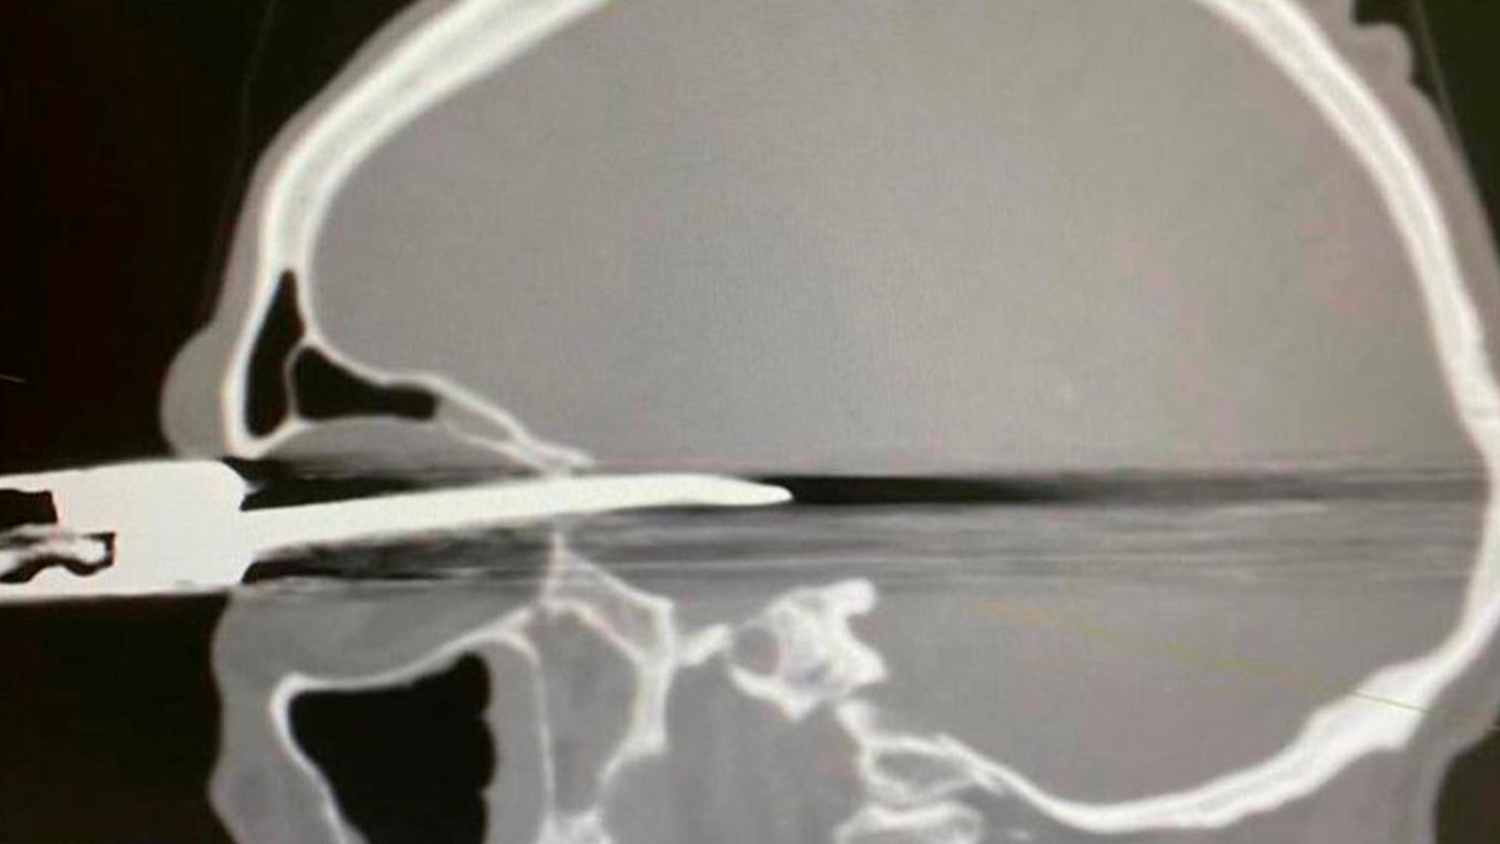

В Кабардино-Балкарии врачи спасли мужчину с ножом в глазу

Врачи Республиканской клинической больницы (РКБ) в Нальчике спасли пациента с проникающим ранением глазницы и черепа, сообщается в Instagram больницы.

После обследования был поставлен диагноз — «проникающее ножевое ранение правой орбиты, полости черепа субарахноидально-паренхиматозное кровоизлияние в правой лобно-височной области с прорывом крови в желудочковую систему. Перелом задней стенки правой орбиты со смещением фрагментов. Инородное тело правой орбиты, полости черепа».

Сначала врачи извлекли нож и обработали рану, затем произвели дренирование раны желудочковой системы головного мозга, то есть удалили жидкое содержимое.

В операции участвовали нейрохирурги, офтальмологи, анестезиологи. Состояние пациента стабильное.